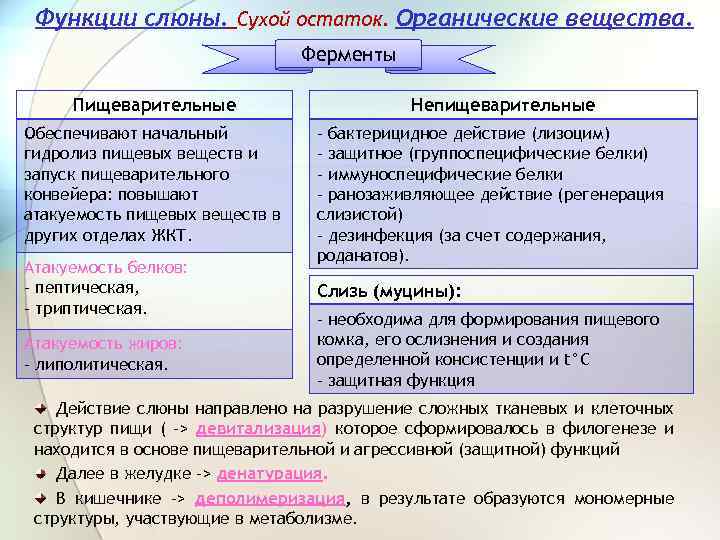

Функции слюны. Сухой остаток. Органические вещества. Ферменты Пищеварительные Обеспечивают начальный гидролиз пищевых веществ и запуск пищеварительного конвейера: повышают атакуемость пищевых веществ в других отделах ЖКТ. Атакуемость белков: - пептическая, - триптическая. Атакуемость жиров: - липолитическая. Непищеварительные - бактерицидное действие (лизоцим) - защитное (группоспецифические белки) - иммуноспецифические белки - ранозаживляющее действие (регенерация слизистой) - дезинфекция (за счет содержания, роданатов). Слизь (муцины): - необходима для формирования пищевого комка, его ослизнения и создания определенной консистенции и t°C - защитная функция Действие слюны направлено на разрушение сложных тканевых и клеточных структур пищи ( -> девитализация) которое сформировалось в филогенезе и находится в основе пищеварительной и агрессивной (защитной) функций Далее в желудке -> денатурация. В кишечнике -> деполимеризация, в результате образуются мономерные структуры, участвующие в метаболизме.